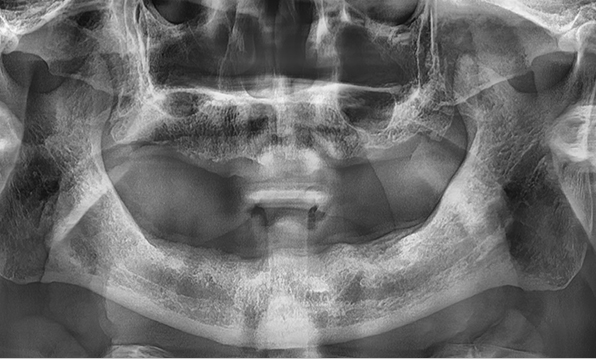

잇몸뼈가 얇은 상태

-

잇몸뼈 충분히 이식 후 임플란트 식립

성공을 위한 노하우, 잇몸뼈 재건 기술

전체 임플란트를 해야하는 환자들은

대부분 고령의 환자들로 오랜 틀니 사용

또는 노화로 인해 치조골이

거의 남아있지 않는 경우가 많습니다.

이 때, 치조골 이식을 병행하여 잇몸뼈 재건 후 안정적인 임플란트 식립을 하고 있습니다.

치료기간 : 2021.04.12~2021.09.15